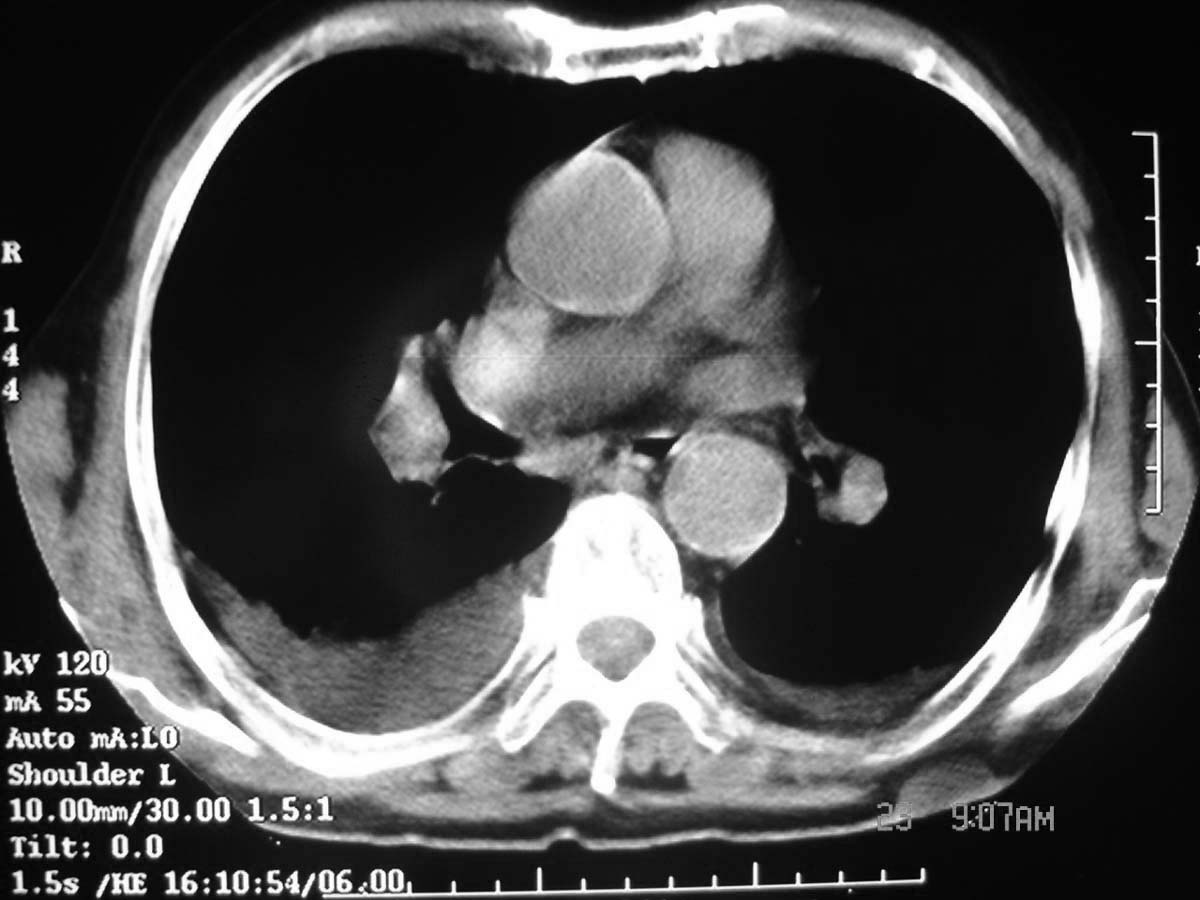

以下是引用守望可可西里在2006-11-23 14:33:00的发言:[br][br] 糖尿病病人很容易继发结核,病人又有双侧胸膜增厚、粘连、胸腔积液以及双上肺的斑片状、条索状影结核病灶影,以一元论考虑,右下肺病变首先考虑干酪性肺炎,可以正规抗炎治疗后复查,排除一般的肺炎。